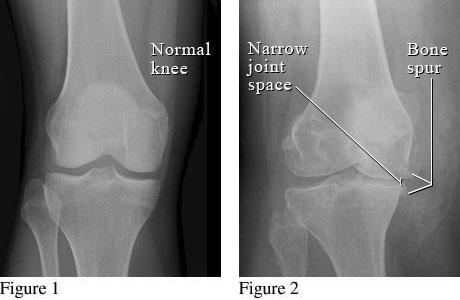

X-Ray of Osteoarthritis of the Knee